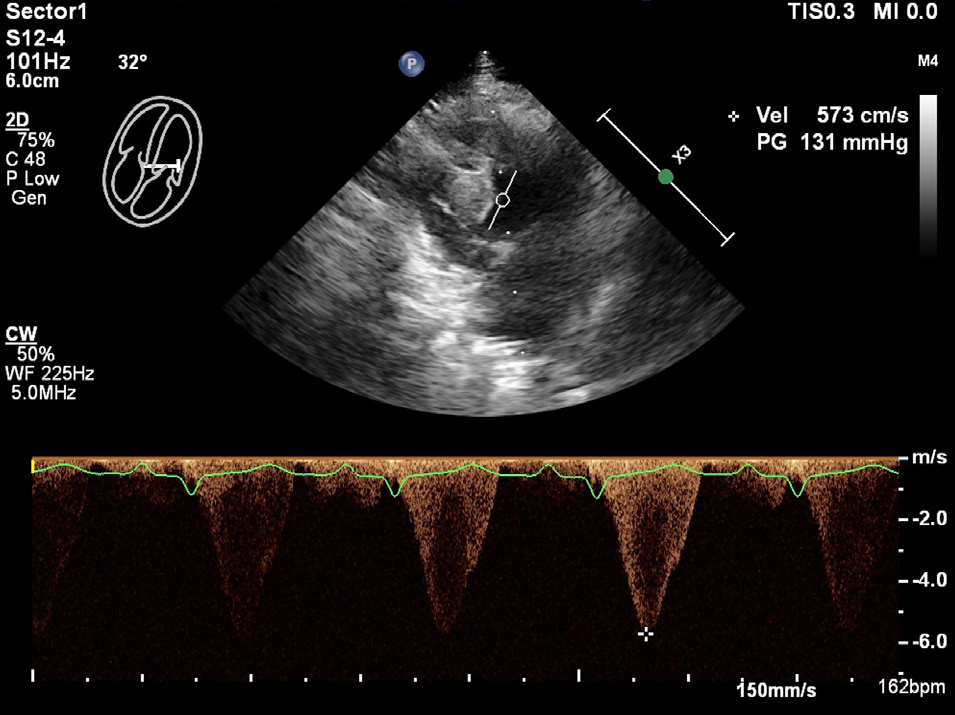

存在二尖瓣收缩期前向运动,伴有严重的动态左心室流出道梗阻(峰值流速5.73米/秒;压力梯度131毫米汞柱;下图)。

↑ 左心室流出道的连续波多普勒超声心动图图像。测得的峰值流速为5.73米/秒,压力梯度为131毫米汞柱,符合严重的动态左心室流出道梗阻。

超声心动图检查发现室间隔和左心室后壁显著增厚,而心尖区域的左心室游离壁局部变薄至约1.6 mm,且心肌运动减弱,提示存在THyMS。此外,左心房收缩功能下降,左心房与主动脉比值增加,左心房内还出现了自发性超声显影,提示血栓形成风险增加。心电图显示左前分支阻滞,表现为左轴偏移,II、III和aVF导联出现小R波和深S波。

LAFB是由于左前分支传导延迟引起的心脏传导异常,通常与心肌纤维化和重构有关。本病例中,LAFB和THyMS的共存提示两者可能存在共同的病理生理机制,即心肌纤维化和重构可能同时影响了心脏的电传导系统和心肌结构。此外,该猫还表现出严重的左心房扩张、左心室流出道梗阻和二尖瓣前向运动,这些均为HCM的典型表现,且与不良预后相关。